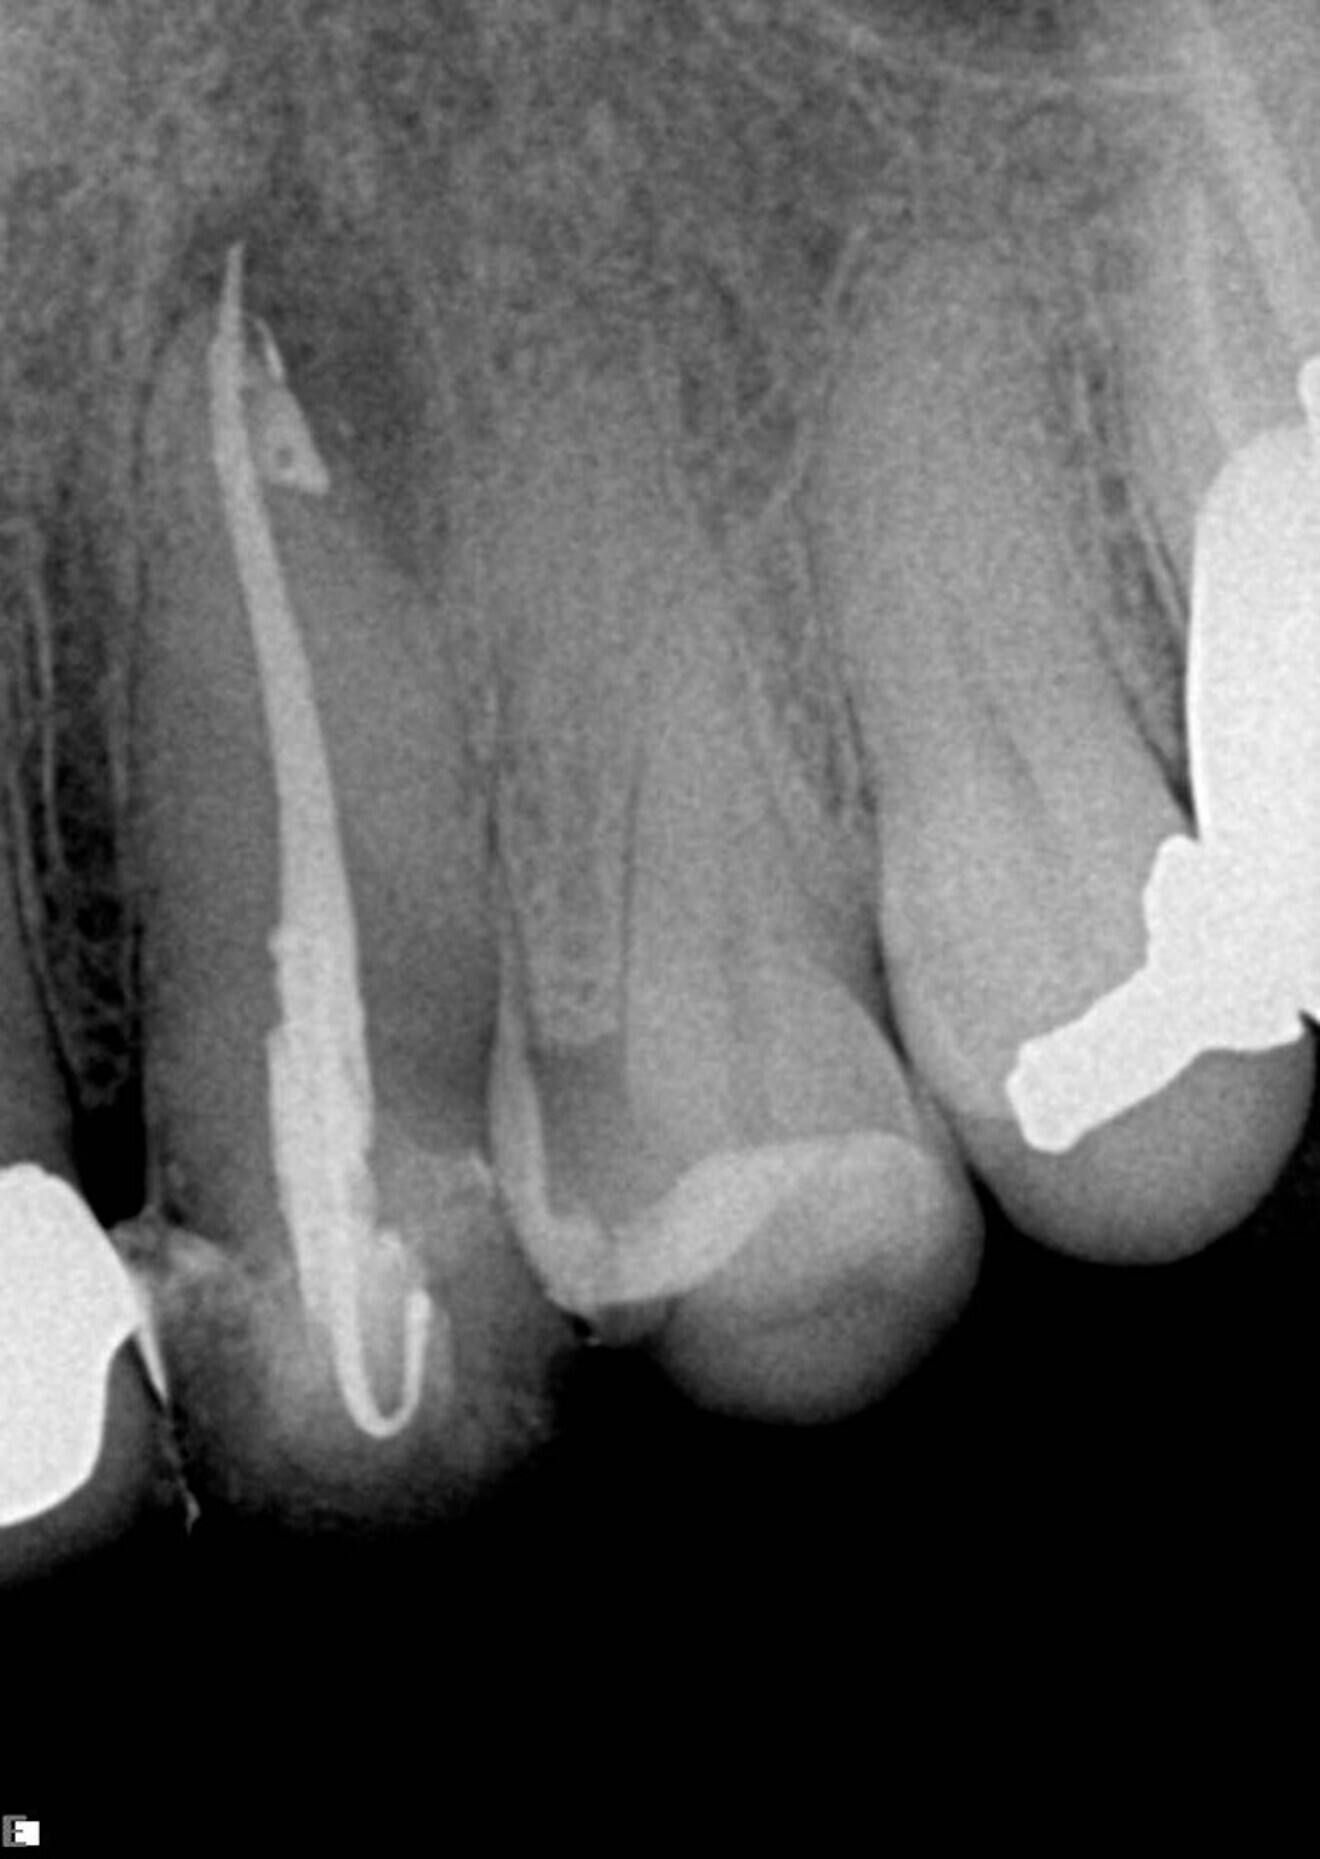

In this example case, the patient was referred by his treating dentist, who had penetrated deep into the roots in trying to find the canals and was not successful, but fortunately no perforation had occurred (Fig. 8). Under the microscope and using ultrasonic tips, the canals were made accessible. On the radiograph, we can see that the canals, especially the mesial ones, are narrow and have small curves, particularly apically. The real challenge in this case was maintaining the original shape of the canal. For those reasons, the sequence with the 0.04 taper was chosen. Treatment was initiated with the 25/0.08 Traverse orifice opener, followed by a 8 K-File for working length determination. The 13/0.06 Traverse file was used all the way to the end of the working length, followed by the 20/0.04 and 25/0.04 ZenFlex files, both taken to working length. For apical enlargement, the 30/0.04 ZenFlex file was used.

A medium cone was used as the master cone in the distal root, and fine-medium cones were used in the mesial root. A full sequence of irrigation was used during the treatment, and the system, which included a deep isthmus between the mesial roots, was filled in multiple levels from the middle to the apex, achieving beautiful 3D obturation (Fig. 9).

Fig. 8

Fig. 9